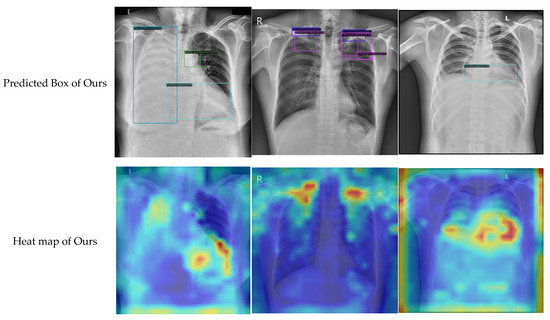

Finally, to carry out an interpretative analysis of our model, we used Grad-CAM [13] to generate a heat map visualization. Some representative examples of our model and the baseline are presented in Figure 10. By analyzing the results, the following conclusions could be drawn. First, compared with the baseline, the heat map generated by our model was more consistent with the ground truth. Second, the results of our qualitative prediction box also showed a certain correspondence with the heat map. This implied that Grad-CAM had a certain faithfulness to our model, and that the proposed method had good reliability. In general, the heat map produced with our method highlighted the discriminative regions that were more consistent with the visual judgment of radiologists, although it must be noted that this method of comparison was a relatively subjective way of evaluating the proposed method.

Figure 10.

The heat map visualization for proposed model and baseline.